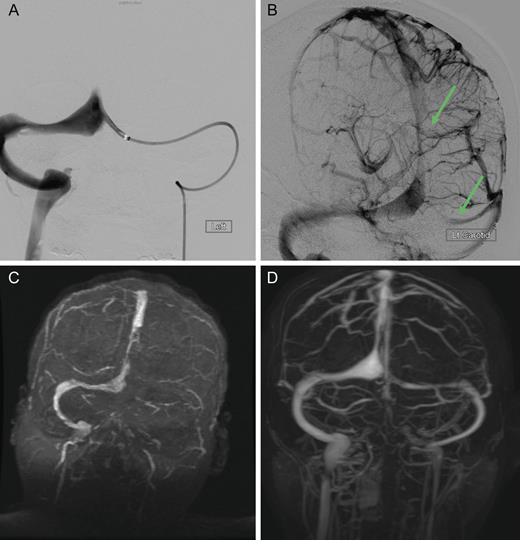

Dural sinus venogram (A) Prior to endovascular mechanical thrombectomy (B) Post mechanical thrombectomy. (C) Pre-intervention MRV demonstrating complete occlusion of the left transverse sinus and near occlusion of the posterior portion of the superior sagittal sinus. (D) Post-intervention MRV demonstrating persistent recanalization of the left transverse and sigmoid sinuses, along with much improved flow in the posterior superior sagittal sinus. Note the recanalization of the left transverse sinus and the much improved flow in the superior sagittal sinus.

The patient was treated emergently with endovascular mechanical thrombolysis with technical success (Fig. 3A and B), followed by systemic anticoagulation therapy. Post-intervention MRV demonstrated persistent recanalization of the left transverse and sigmoid sinuses, along with much improved flow in the posterior superior sagittal sinus (Fig. 3D).

Main treatment options are anticoagulation, fibrinolytic therapy, thrombolysis (either directly or mechanically) and/or management of intracranial pressure [3]. Heparinization offered mortality rates typically <10%, which was often attributed to the underlying disease rather than CVT. If the patient experiences a raised intracranial pressure or worsened clinical state after anticoagulation, thrombolytic therapy is suggested. Presenting without light perception in either eye, our patient was treated emergently with mechanical thrombolysis followed by anticoagulation therapy (intravenous heparin bridging to coumadin), resulting in the successful recanalization of the left transverse sinus and a much improved flow in the superior sagittal sinus.